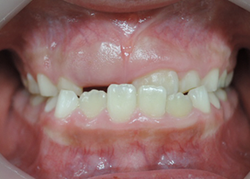

8歳の女子 受け口(下顎前突)

術前

術後

7歳の女子 受け口(下顎前突)

いずれも、顎のラインがスッキリしています。

これは、受け口が改善して筋肉の使い方が通常に戻ったために起こった変化です。

大人ではこの変化は起こりません。